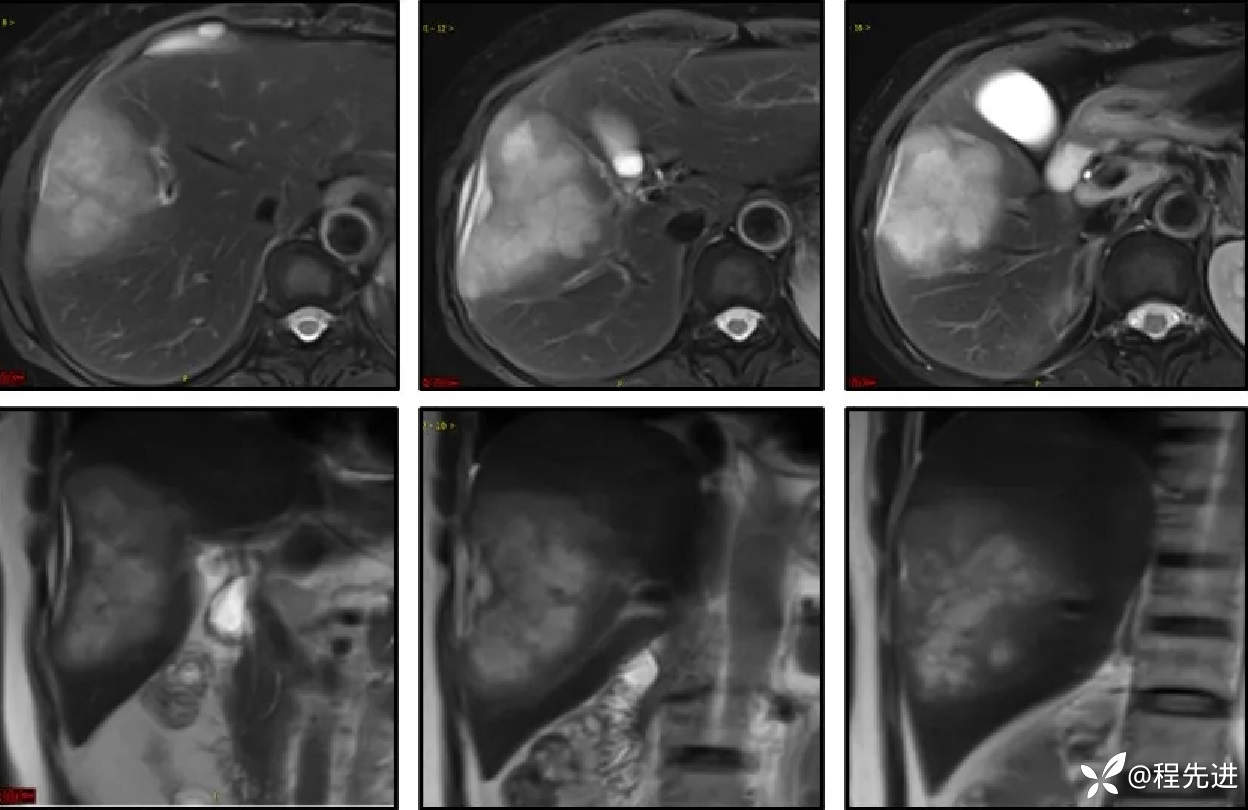

同反相位:

T2:

DWI、ADC: